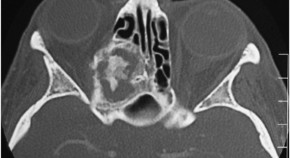

Ophthalmic findings are common features of neurodegenerative disorders, and have emerged as potentially useful biomarkers of disease progression in several conditions. Kersten et al. describe the various afferent visual system and other ophthalmic features of inherited neurodegenerative disorders, focusing on the expanding role of optical coherence tomography in diagnostic imaging of the retina and optic nerve head. They also discuss the ophthalmic manifestations and treatment implications of mitochondrial dysfunction—a feature of many inherited neurodegenerative diseases.